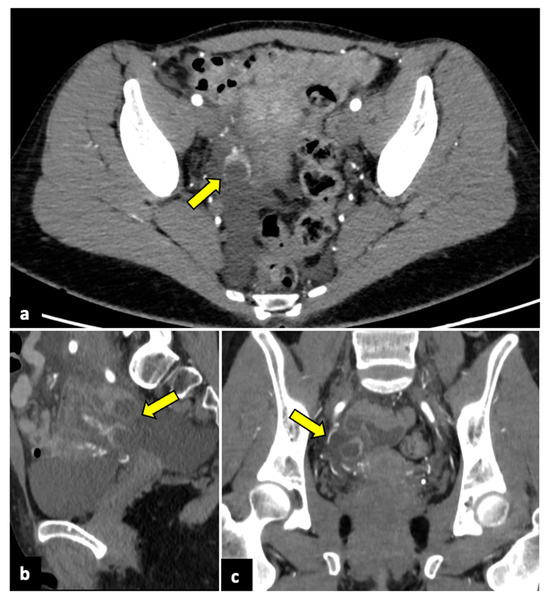

Review

Gynaecological Causes of Acute Pelvic Pain: Common and Not-So-Common Imaging Findings

by Paolo Niccolò Franco, Alejandra García-Baizán, María Aymerich, Cesare Maino, Sofia Frade-Santos, Davide Ippolito and Milagros Otero-García

Life 2023, 13(10), 2025; https://doi.org/10.3390/life13102025 - 9 Oct 2023

Cited by 14 | Viewed by 11064

In female patients, acute pelvic pain can be caused by gynaecological, gastrointestinal, and urinary tract pathologies. Due to the variety of diagnostic possibilities, the correct assessment of these patients may be challenging. The most frequent gynaecological causes of acute pelvic pain in non-pregnant [...] Read more.

In female patients, acute pelvic pain can be caused by gynaecological, gastrointestinal, and urinary tract pathologies. Due to the variety of diagnostic possibilities, the correct assessment of these patients may be challenging. The most frequent gynaecological causes of acute pelvic pain in non-pregnant women are pelvic inflammatory disease, ruptured ovarian cysts, ovarian torsion, and degeneration or torsion of uterine leiomyomas. On the other hand, spontaneous abortion, ectopic pregnancy, and placental disorders are the most frequent gynaecological entities to cause acute pelvic pain in pregnant patients. Ultrasound (US) is usually the first-line diagnostic technique because of its sensitivity across most common aetiologies and its lack of radiation exposure. Computed tomography (CT) may be performed if ultrasound findings are equivocal or if a gynaecologic disease is not initially suspected. Magnetic resonance imaging (MRI) is an extremely useful second-line technique for further characterisation after US or CT. This pictorial review aims to review the spectrum of gynaecological entities that may manifest as acute pelvic pain in the emergency department and to describe the imaging findings of these gynaecological conditions obtained with different imaging techniques. Full article